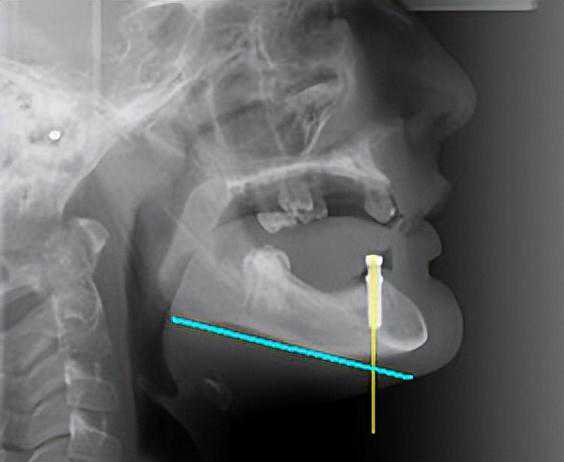

除了常规体检外,CBCT检查也是种植牙术前的必做项。这里科普一下,一家没有CBCT检查设备的医院,是没有种植手术资格的,别回头,赶紧跑。

做完CBCT后,医生才能知道你的骨骼情况是否合适,有的人颌骨条件不合适,不能做。有的人只是骨量不足,就需要先做骨粉填充手术,之后才能安排种植。

种植前的手术规划